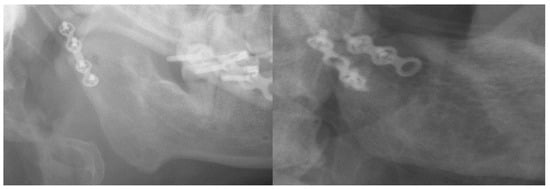

2. Materials and Methods

3. Results